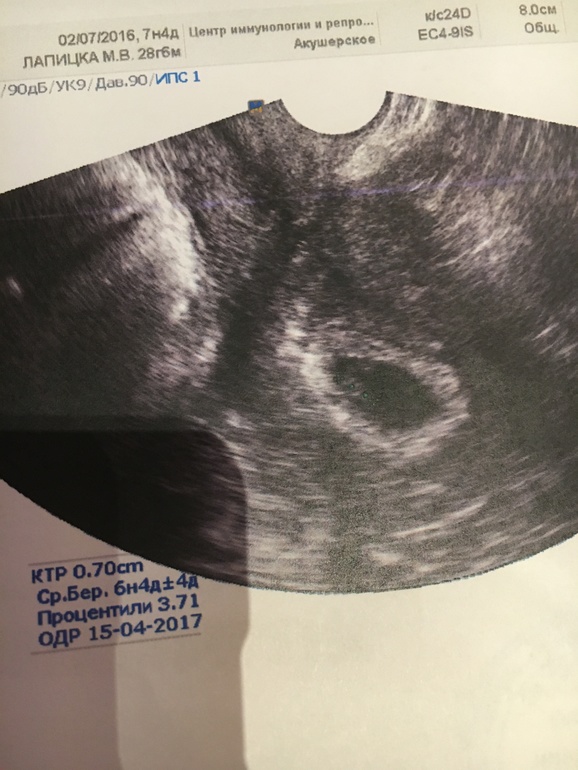

Первое УЗИ

УЗИ, КТГ, доплерВсем привет , теперь официально можно писать в эту группу ) Были на первом УЗИ сегодня в ЦиР , визуализировали одного малышика с сердцебиением 146 ударов в минуту . С дочкой на этом сроке было всего 122 удара. Срок поставили меньше, 6 недель и 4 дня, но у меня была поздняя овуляция , как раз на недельку позже обычного. И первое фото на память ) ничего не понятно правда, но пусть будет :)